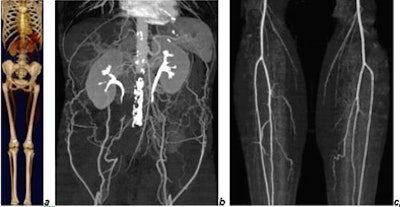

"Now the question is do we really want that (maximum speed), and the answer is no," he said, showing a whole-body image acquired in 16 seconds on a 64-detector scanner -- that had outrun the contrast bolus.

"Since we usually don't know what the patient has when we perform a peripheral CTA, that's why we do the exam. It makes sense to try to do something about the scanning speed," Prokop said. "Two solutions: use a longer delay -- wait more time before you start scanning -- or scan slower, and that's actually what we're doing. We use a lower pitch, and try to keep the whole-body scan in the range of 30-40 seconds...."

![]() |

| CTA of chest, abdomen, and legs (150-cm scan length) in a patient with Leriche's syndrome examined with 16 x 0.75-mm collimation within 50 seconds. Images courtesy of Dr. Mathias Prokop. |